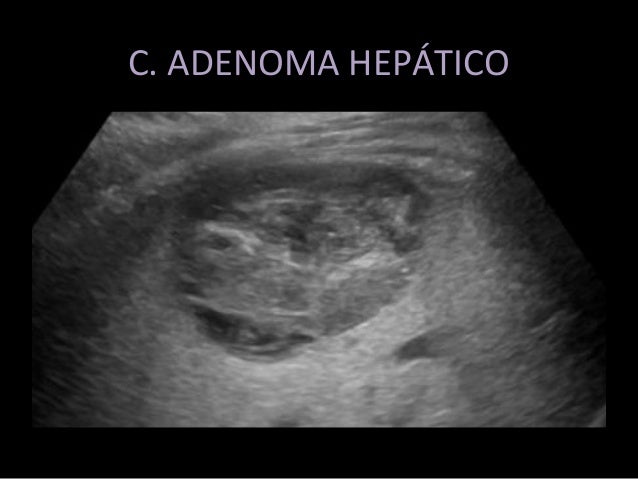

Tumores hepáticos sólidos comunes artículos intramed. O sudeste da Ásia, japão e África do sul apresentam uma incidência particularmente alta de carcinoma hepatocelular, enquanto que nos estados unidos, grã bretanha. Imaging features of fibrolamellar hepatocellular carcinoma. Fibrolamellar hepatocellular carcinoma (hcc) is a unprecedented number one liver tumor, which significantly differs from traditional hcc. This article critiques the molecular cytogenetics, pathology, imaging functions, and control of this distinctly uncommon tumor. Organización y financiamiento del sistema de salud en l. A.. 25 gh continuada. Julioagosto 2003. Vol. 2 n.O 4 153 medicina guiada estudio del nódulo hepático aislado x. Xiol ecografía característica y tamaño menor de three cm. Câncer de fígado inca. Apenas 15 a 30% dos pacientes portadores de carcinoma hepatocelular (chc) são passíveis de ressecção cirúrgica definitiva (7) e, mesmo assim, o número de. Leia mais sobre hepatocarcinoma hepcentro.Br. Resumen. El hepatocarcinoma fibrolamelar ocurre principalmente en adolescentes y adultos jóvenes, encontrándose en hígados no cirróticos como forma p.C. Frecuente. Radiologia brasileira tumores hepáticos incomuns ensaio. Introdução o hepatocarcinoma (ou carcinoma hepatocelular chc) é o câncer primário do fígado, ou seja, o câncer derivado das principais células do fígado.